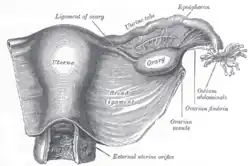

Female reproductive system numbered parts Image showing the right fallopian tube (here labeled the uterine tube) seen from behind. The uterus, ovaries and right broad ligament are labeled.

Image showing the right fallopian tube (here labeled the uterine tube) seen from behind. The uterus, ovaries and right broad ligament are labeled. Cross-section of fallopian tube, stained and viewed under microscope